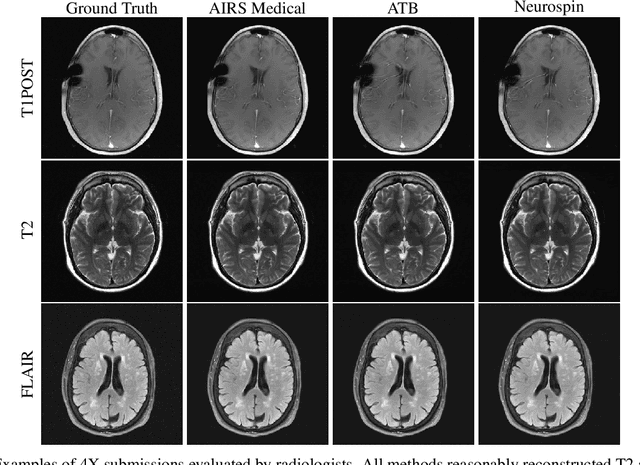

Abstract:Accelerating MRI scans is one of the principal outstanding problems in the MRI research community. Towards this goal, we hosted the second fastMRI competition targeted towards reconstructing MR images with subsampled k-space data. We provided participants with data from 7,299 clinical brain scans (de-identified via a HIPAA-compliant procedure by NYU Langone Health), holding back the fully-sampled data from 894 of these scans for challenge evaluation purposes. In contrast to the 2019 challenge, we focused our radiologist evaluations on pathological assessment in brain images. We also debuted a new Transfer track that required participants to submit models evaluated on MRI scanners from outside the training set. We received 19 submissions from eight different groups. Results showed one team scoring best in both SSIM scores and qualitative radiologist evaluations. We also performed analysis on alternative metrics to mitigate the effects of background noise and collected feedback from the participants to inform future challenges. Lastly, we identify common failure modes across the submissions, highlighting areas of need for future research in the MRI reconstruction community.